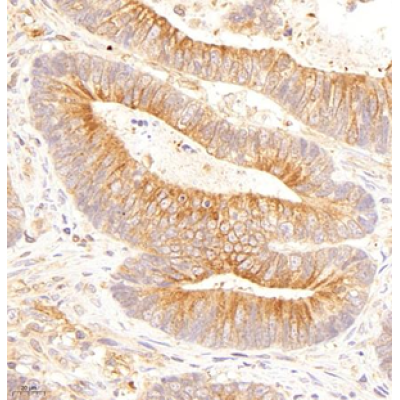

Immunohistochemistry analysis of paraffin embedded human colon cancer using P-α-tubulin (GB14162) at dilution of 1: 200 |